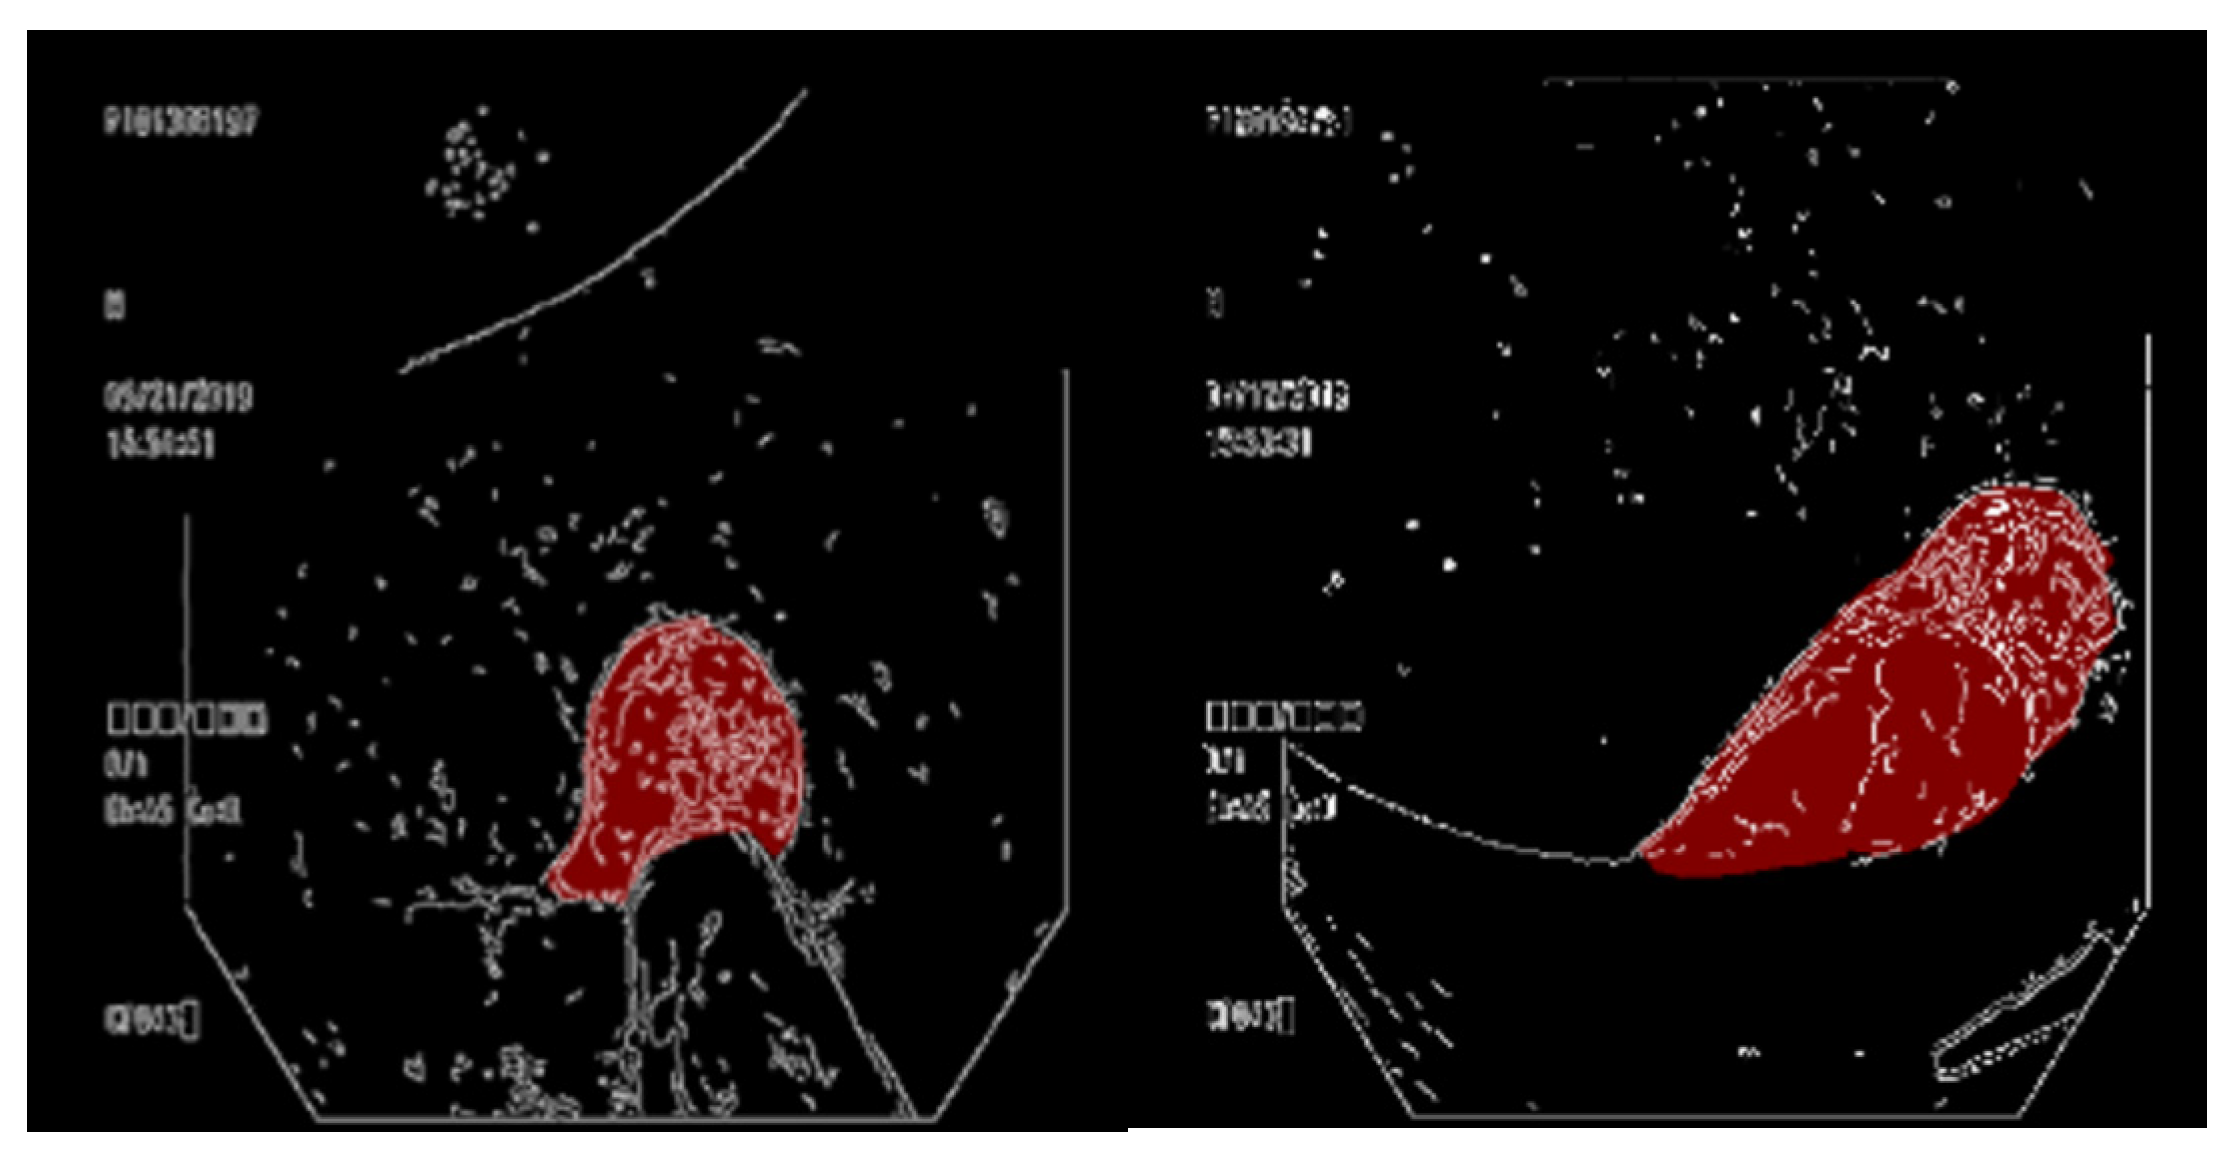

3.4. Overlaying a Contour Map on a Ground Truth Map

3.5. Overlaying the Ground Truth Map onto the Original Image